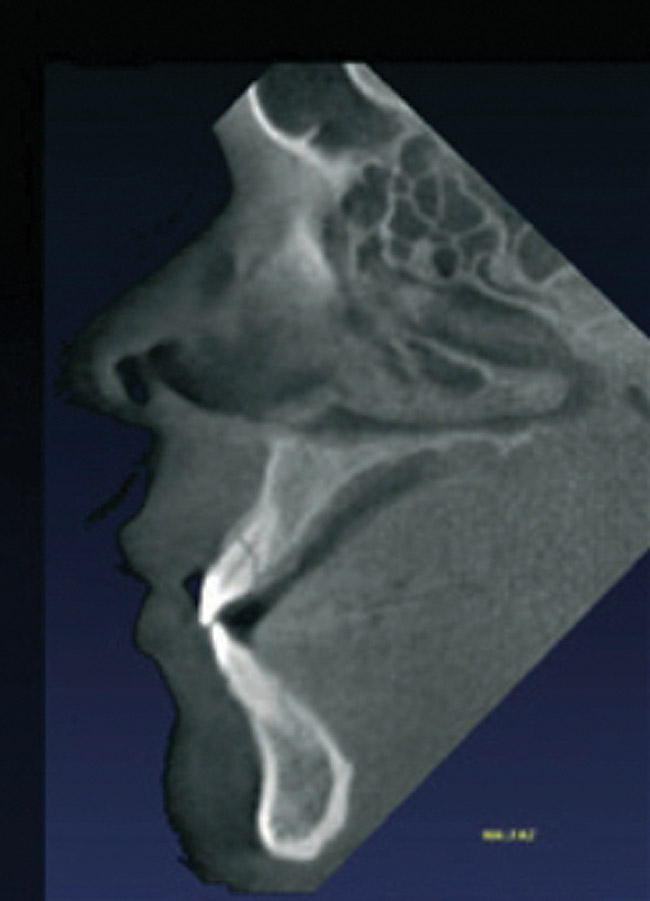

Initially, case studies appeared in the endodontic literature in which patients underwent CBCT imaging for the purposes of diagnosis20-22 and presurgical treatment planning.19 Recent reports have successfully shown the use of CBCT to locate missed canals,23 detect the extent of dentoalveolar fractures,20 identify resorption patterns,22 and compare cystic with granulomatous periapical lesions.17 Figure 2A through Figure 2C show a case in which the missed canal was suggested by periapical radiographs but confirmed with CBCT.24 Similarly in Figure 3A through Figure 3D, the additional diagnostic information attained from CBCT confirmed the diagnosis and extent of the root fracture, which initially was observed in the periapical radiographs (Figure 4A and Figure 4B).20 Notably, the extent of the lingual fracture as well as any alveolar complications could be visualized by CBCT only.

Figure 2a  Another case that clearly shows additional canal anatomy (distolingual root) not easily detected by periapical radiographs. Periapical radiograph depicting possible widened periodontal ligament (A). The CBCT clearly shows the missed canal in all three dimensions (B). The postoperative periapical radiograph shows the re-treatment, which includes the obturation of the distolingual canal24 (C).

Figure 2a

Figure 2b  Another case that clearly shows additional canal anatomy (distolingual root) not easily detected by periapical radiographs. Periapical radiograph depicting possible widened periodontal ligament (A). The CBCT clearly shows the missed canal in all three dimensions (B). The postoperative periapical radiograph shows the re-treatment, which includes the obturation of the distolingual canal24 (C).

Figure 2b

Figure 2c  Another case that clearly shows additional canal anatomy (distolingual root) not easily detected by periapical radiographs. Periapical radiograph depicting possible widened periodontal ligament (A). The CBCT clearly shows the missed canal in all three dimensions (B). The postoperative periapical radiograph shows the re-treatment, which includes the obturation of the distolingual canal24 (C).

Figure 2c